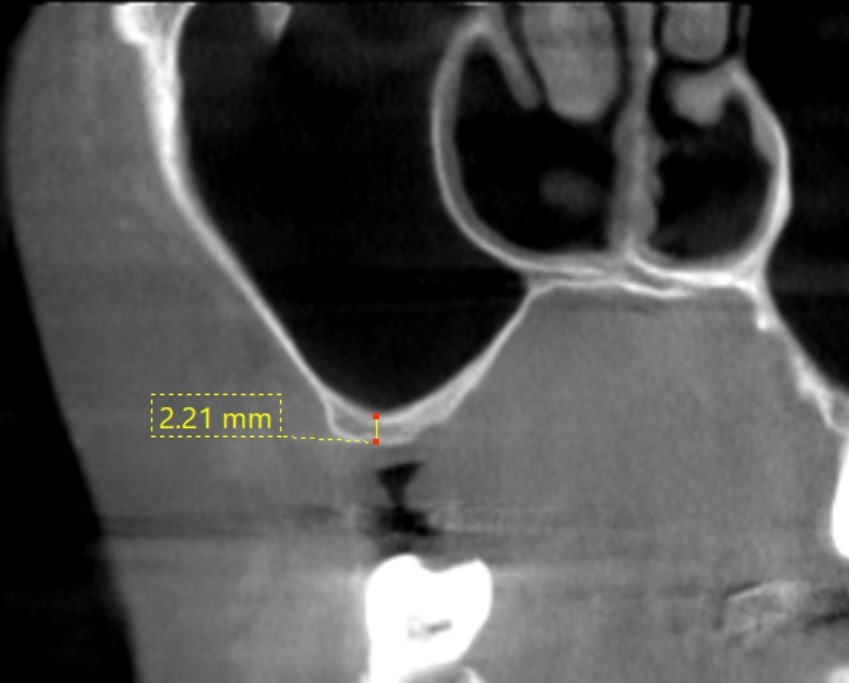

治療前

サイナスリフト GBR

インプラントを埋入する骨の厚みが十分にありません。

治療後

人工の骨を使って骨の厚みを確保し、インプラント治療を行いました。